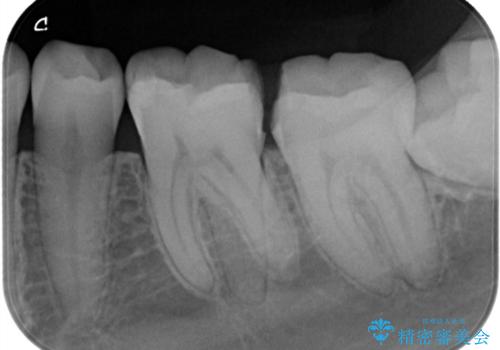

- 他院で虫歯と言われたが、銀歯は患者様自身嫌だということでインターネットで当院のサイトを見ていただき来院されました。

銀歯の治療も悪いわけではありませんが、残念なことに再治療になることがよくあります。

再治療しないためにも、いい型取りの材料を使用し歯の形に適した被せ物にすることをお勧めいたします。